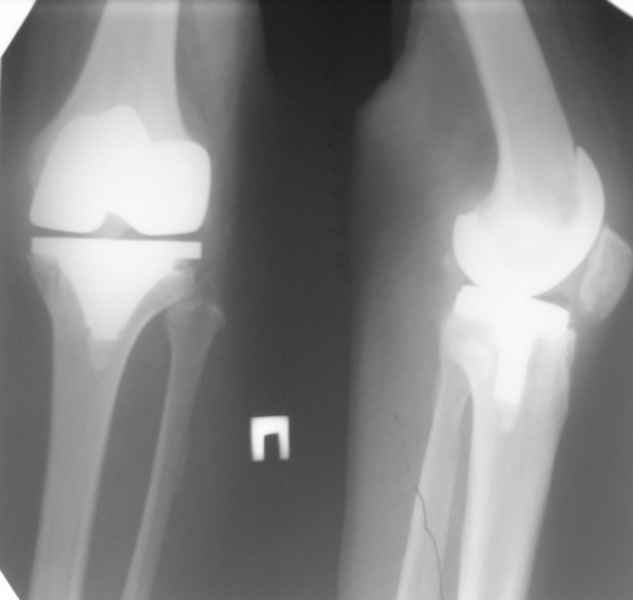

Активная ЛФК. Через 6 месяцев - движения качательные.

Осевая нагрузка практически безболезненна.

Первое время после ревизии периодически беспокоили озноб, локальное повышение температуры в области сустава. В последнее время этого практически нет.

В анализах - придраться можно только к СОЭ - 27.

Есть вопросы к установке протеза.

Скорее всего тибиальное плато было не конца резецировано и в задненаружных отделах осталась ступенька. Это привело к тому, что тибиальный компонент завалился на варус.

Можно пойти на повторную ревизию, удалить большеберцовый компонент и поставить его правильно, но как справиться с артрофиброзом?